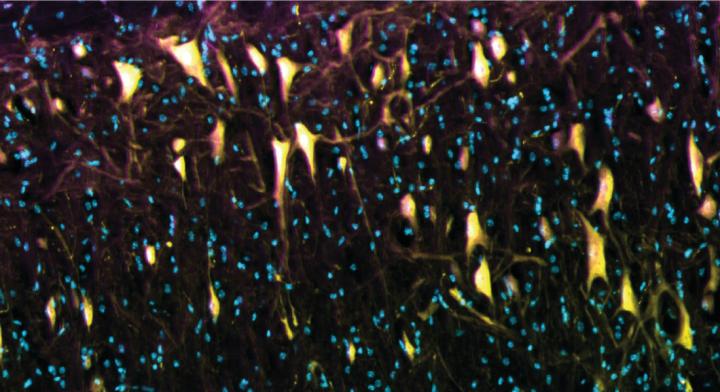

image: The image shows the compound Tat-P4-(C5)2 after an injection into the spinal cord. The compound (purple) penetrates the nerve cells of the spinal cord (yellow), but not the surrounding cells (the cell nuclei are blue).

The compound developed by the researchers is a so-called peptide named Tat-P4-(C5)2. The peptide is targeted and only affects the nerve changes that pose a problem and cause the pain.